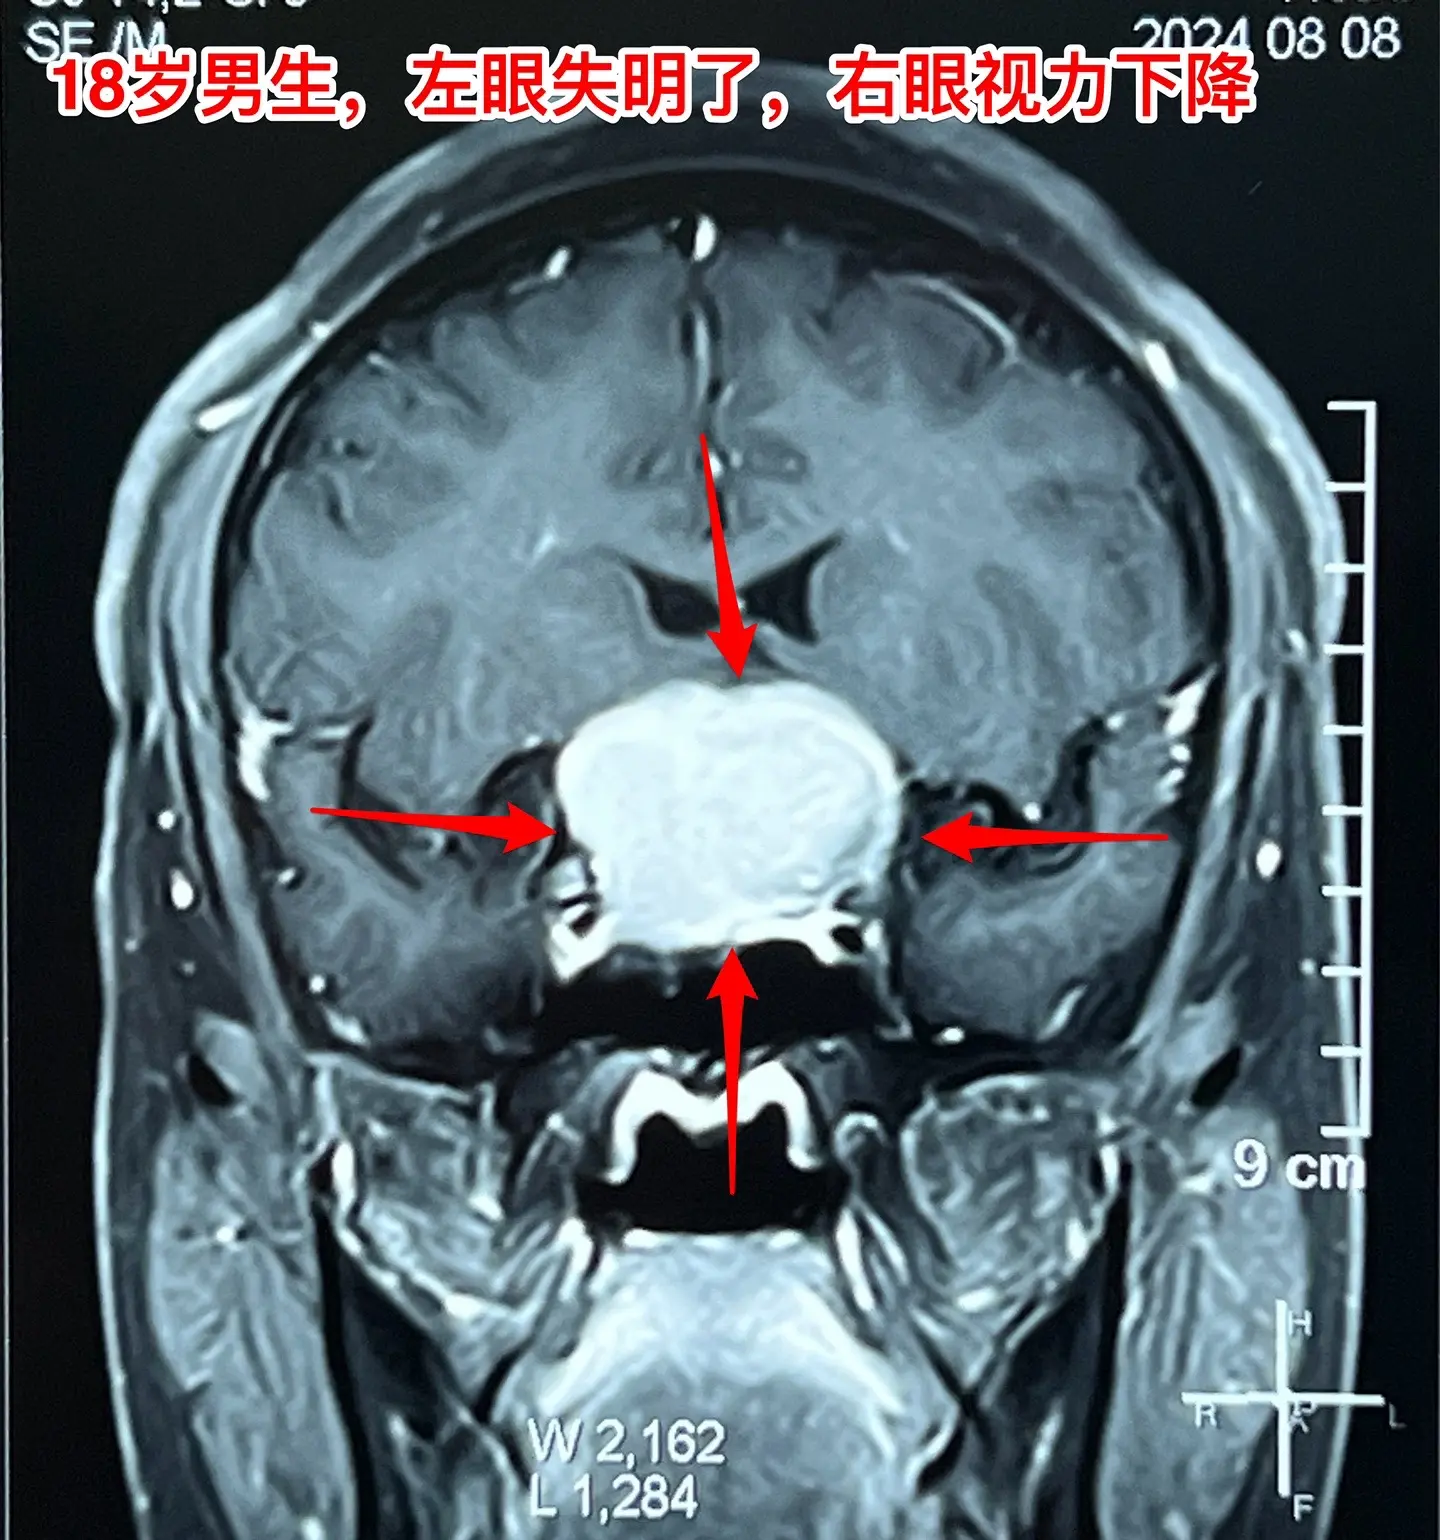

男生高考后想打工,居然发现脑部长瘤了。18岁四川男生,高考后到北京来投奔姑姑,准备到北京打工。 小伙子命苦啊,幼时父亲因病离世,母亲离家,他和奶奶一起生活、长大。 高考后小伙子到北京来投奔姑姑,准备打工,姑姑已经在北京安家了。 姑姑发现小孩子的眼睛似乎出了问题,视力不好,看手机比较困难。仔细询问,才知道他的左眼已经失明了差不多三个月了,一年多前他的右眼视力也明显下降了,这个粗心的孩子居然没有告诉家人。 到北京的医院检查,发现脑部长瘤了,见图。真是祸不单行!瘤体积不小了,小孩子除了视力差之外,精神也差。八月份住院准备做手术,作化验发现尿糖四个+,血转氨酶很高、胆红素也高。用药治疗了一段时间化验值才有好转。 直到九月二号才作手术。手术中发现这个病灶没有钙化,不是典型的颅咽管瘤。很幸运的是病灶完全切除了,而且垂体和垂体柄、下丘脑均保护完好。